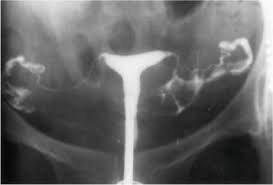

O que é o exame: A histerossalpingografia nada mais é do que um raio-x contrastado da cavidade uterina e de suas tubas. Ele é realizado em série, com a injeção de um líquido (contraste iodado) através do orifício do colo do útero, com o auxílio de um catéter (sonda) fino. É um dos exames mais antigos existentes na rotina da investigação do casal infértil, sendo utilizado há praticamente um século. Apesar de tão antigo, ainda é o melhor para avaliar a anatomia das tubas uterinas, não existindo outro exame que possa nos dar a mesma qualidade de informação sobre esta estrutura. A histerossalpingografia tem como principal objetivo avaliar a morfologia das tubas uterinas e, através desta análise, inferir sobre sua função reprodutiva. Pode também oferecer dados sobre a anatomia uterina, como a presença de mal-formações Müllerianas (útero bicorno, unicorno, septado etc), presença de pólipos ou miomas e sinéquias uterinas. O resultado do exame é um verdadeiro divisor de águas entre os tratamentos. Se estiver normal, os tratamentos podem ser de menor complexidade ("in vivo"), mas caso tenha alterações, devemos partir para os procedimentos mais complexos ("in vitro"). Medos e anseios: É muito comum no consultório receber pacientes que tem verdadeiro terror ao ouvir falar neste exame. Quantas e quantas vezes não ouvi a frase: "faço qualquer coisa, mas não me peça para repetir este exame!". De certa forma, não posso deixar de tirar a razão das minhas pacientes. A histerossalpingografia quando não é bem indicada e bem realizada, é extremamente dolorosa e desconfortável. Assim, é obrigação do médico que solicita o exame explicar à paciente como ele é feito e para que está sendo solicitado. Vale ressaltar que quando o exame é feito seguindo rigorosos critérios e por médicos experientes e com bons equipamentos, não há queixa de dor. Cuidados ao realizar o exame: